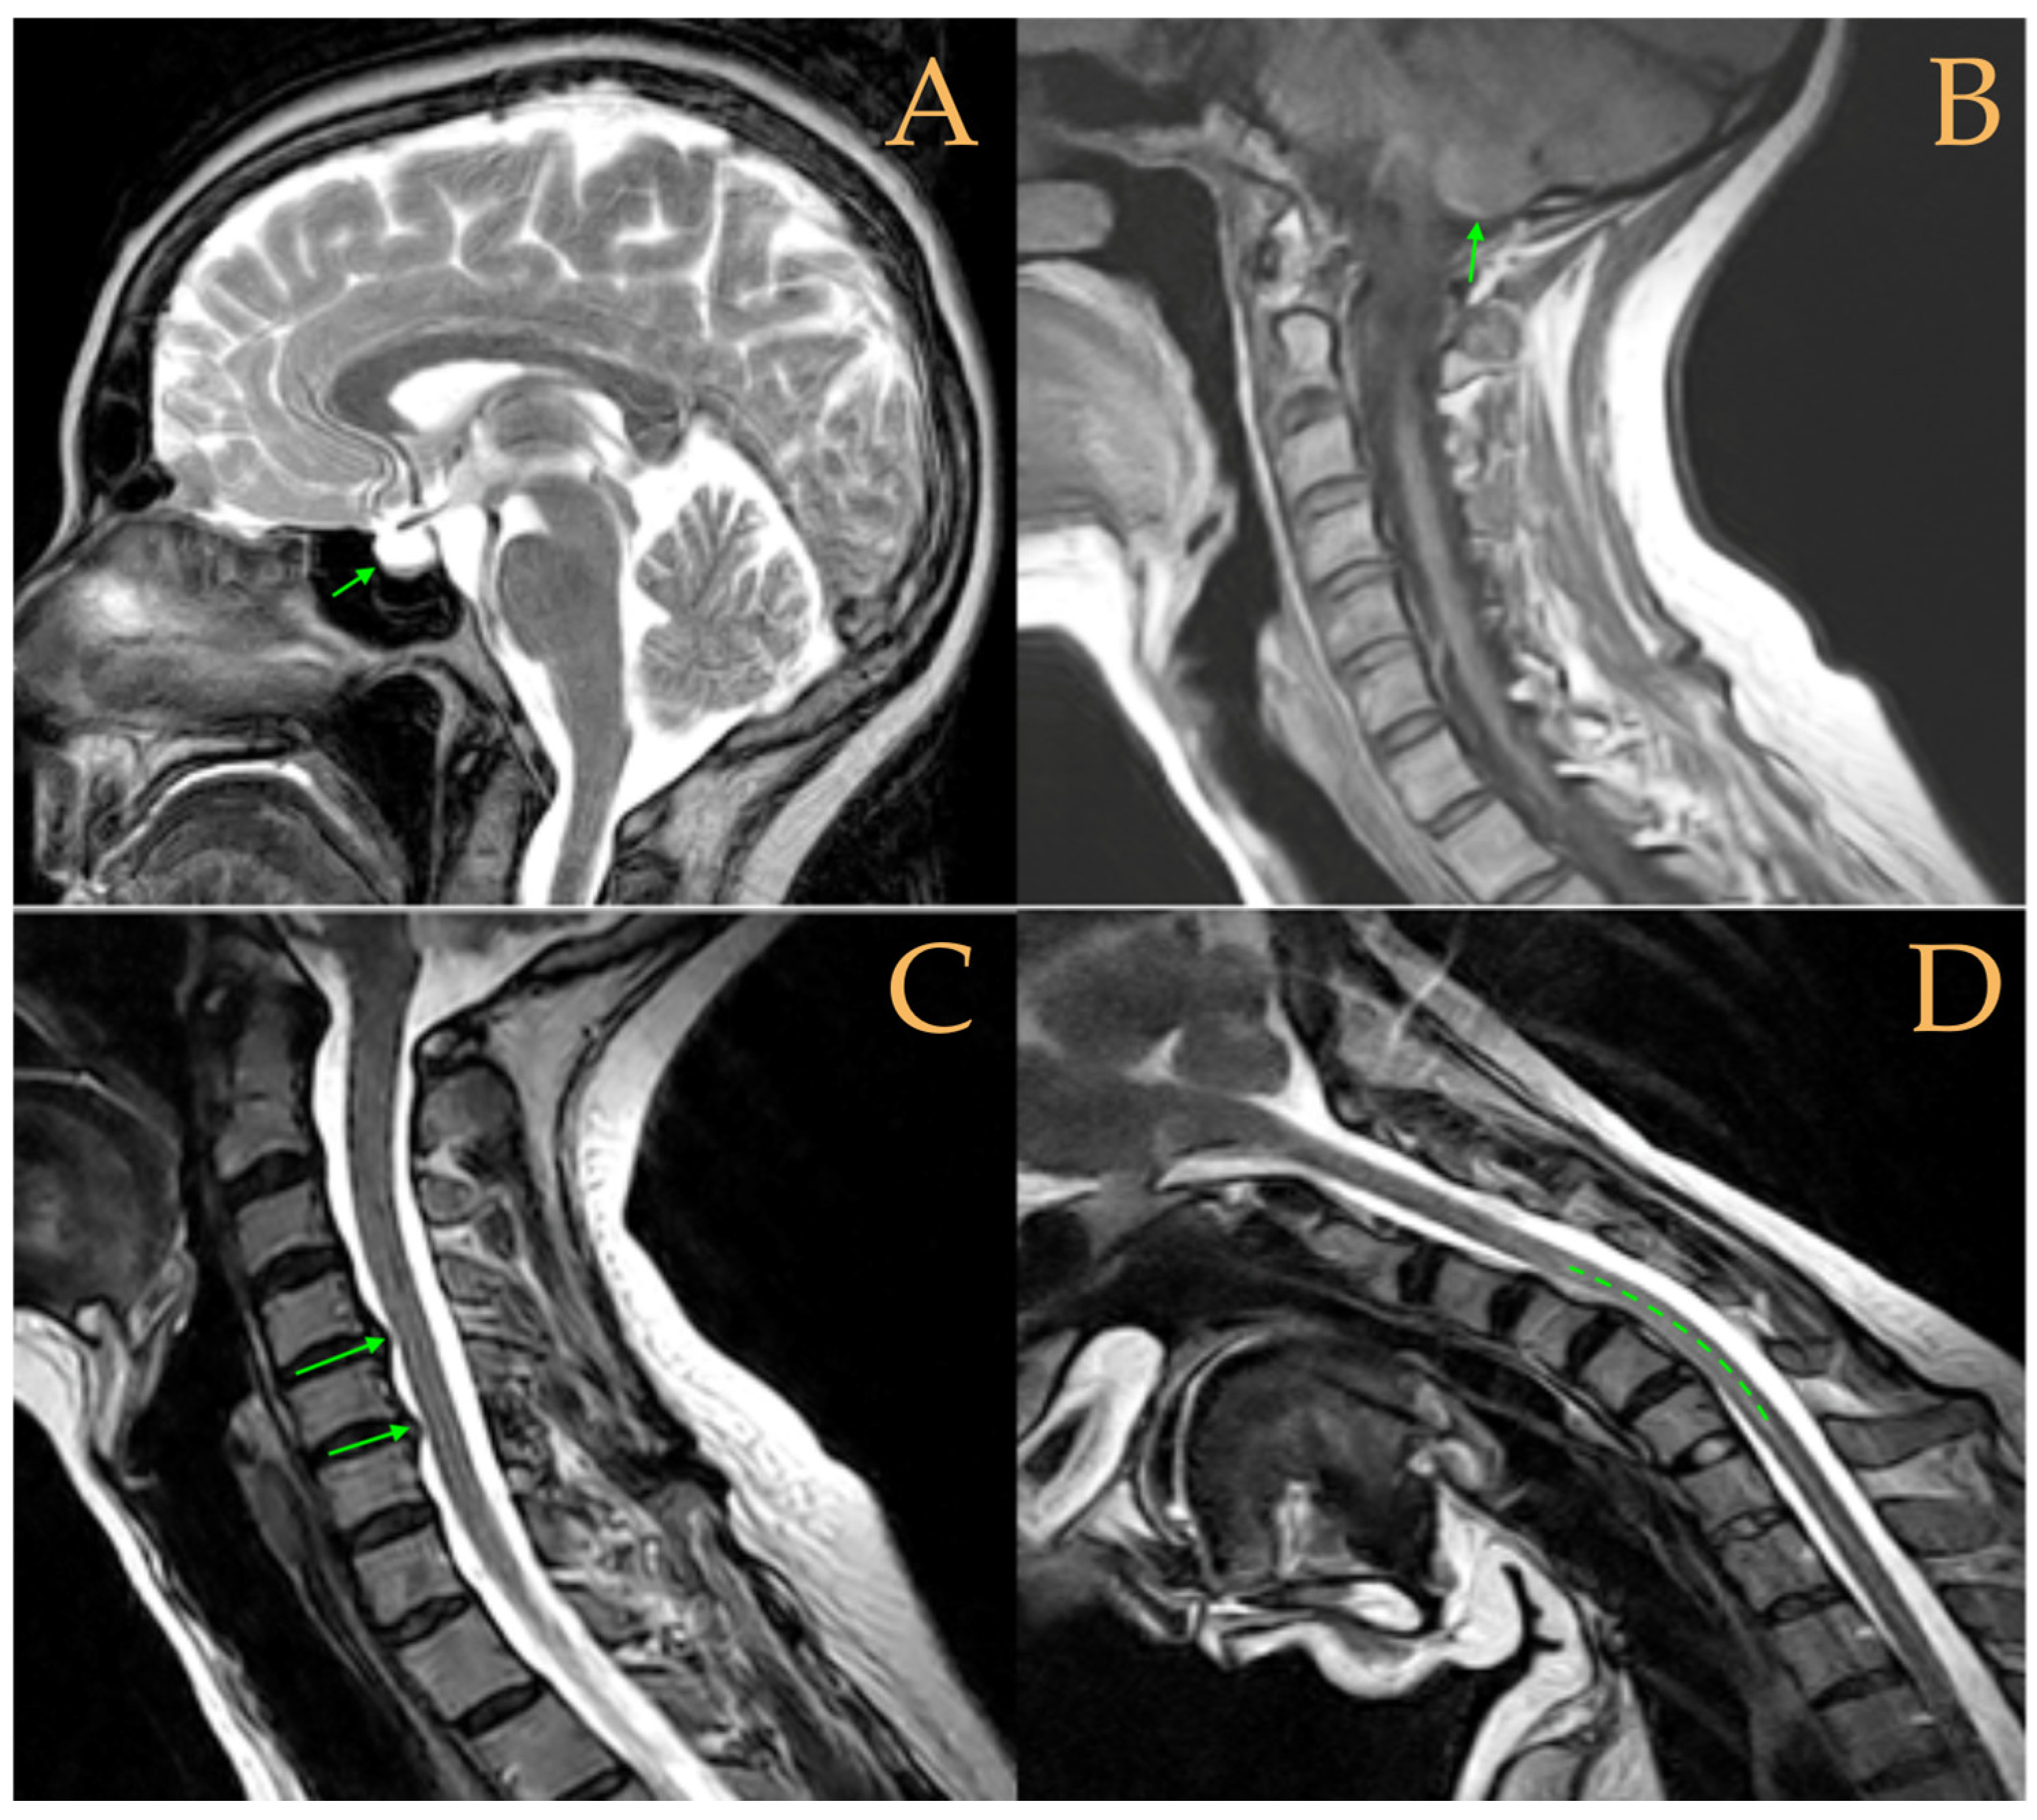

The cranio-vertebral magnetic resonance showed empty sella turcica, discrete descent of the cerebellar tonsils, C4-C5-C6 disc protrusions and cervical hypermobility with a tense medullary aspect in flexion in the incorporated dynamic test, and conus medullaris at the height of the TH12-L1 disc (Figure 3). No scoliosis was observed in the full-spine X-rays. The patient was not operated on. Cases 8 and 9 were very similar and involved previously diagnosed cranio-cervical and atlantoaxial instability. The patient used a cervical collar, as she was afraid that she might suffer spontaneous cervical luxation.

Figure 3.

Imaging of patient 3. A: Empty sella turcica (arrow); B: discrete descent of the cerebellar tonsils (arrow); C: C4C5 and C5C6 disc protrusions (arrows); and D: tense spinal cord in cervical flexion (interrupted line).